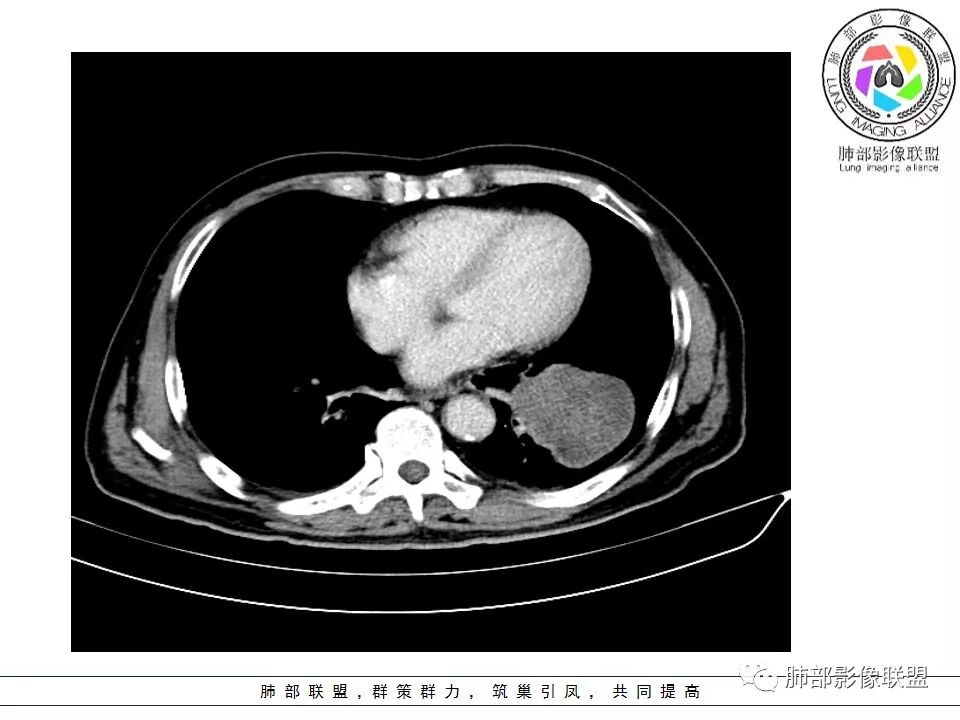

1.左肺下叶近肺门区肿块,肿块外围大,内带小,提示外围向中央生长,符合周围型SCLC沿支气管方向生长。

2.病灶边缘光滑,未见明显分叶、毛刺,符合神经内分泌癌、癌肉瘤及间叶来源肿瘤。

3.病灶内密度偏低,穿行血管未见明显异常,轻度不均匀强化,为乏血供病灶。病灶内可疑坏死区,未见空洞;乏血供符合SCLC,但坏死区不符合。

4.病灶区支气管以受压推移为主,管腔不规则,腔内通而不畅,提示病灶粘膜下为主,符合SCLC迁徙蔓延或间叶来源肿瘤。

5.病灶内有血管走行,血管局部受压,但是强化考虑为乏血供,提示病灶内肺动脉并不是供血血管,只是病灶侵袭性强把血管包埋而已,为血管包埋征;血流面光滑,血管包埋符合SCLC。

6.左肺门淋巴结肿大,与病灶局部融合分界不清,呈冰冻肺门;而纵隔内未见肿大淋巴结,冰冻肺门符合SCLC,但是病灶主体那么大,纵隔内没有明显肿大淋巴结,不是很符合SCLC娘小崽大的特点。

7.未见明显阻塞性炎症及阻塞性肺不张,更加提示病灶从外围向中央侵犯,符合SCLC罕见阻塞性肺不张。